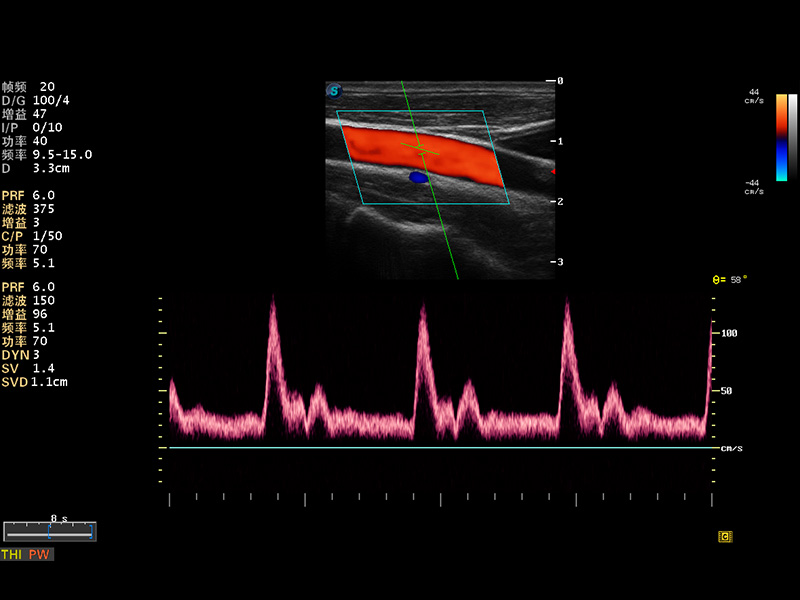

S8 EXP便攜式彩色多普勒超聲診斷儀是開立醫(yī)療研發(fā)的高端全身應(yīng)用型便攜彩超。高通道的VIS平臺融合可視化(Visual)、智能化(Intelligent)和人性化(Smart)的特點,配以開立醫(yī)療自主研發(fā)生產(chǎn)的探頭大家族,使您能夠快速、準(zhǔn)確的獲得病人信息,提高工作效率的同時減輕疲勞。

成像技術(shù)

多波束形成器

μ-Scan微米成像

諧波成像

實時寬景成像

空間復(fù)合成像

3D/4D成像